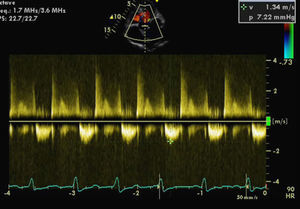

For a more accurate assessment of MV function, TEE was performed (with HR 120–150bpm) (Figures 2 and 3), which showed the MV with a Carpentier ring and leaflet degeneration and redundancy, good opening in diastole but with SAM leading to LVOT obstruction by the anterior leaflet, and severe regurgitation (vena contracta 8mm). The aortic valve was tricuspid, with good opening and mild regurgitation. The left atrial appendage was free of thrombi.